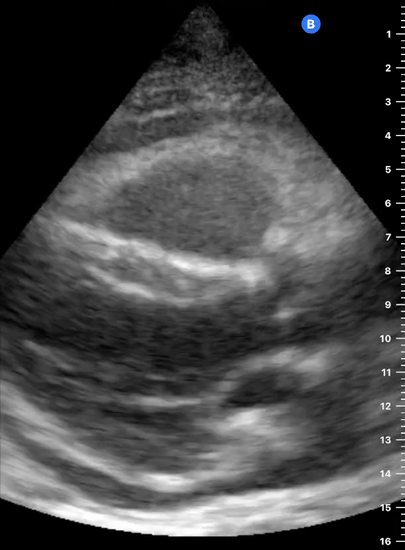

PITFALLS & PLEURAL EFFUSIONS

A common error is to confuse a pericardial fat pad with effusion. Fatty tissue has a heterogeneous echotexture, moving in coordination with the myocardium, and it cannot be tracked around the heart, especially posteriorly and to the apex. Another pitfall is misinterpreting a pleural effusion as a pericardial effusion. However, they can be differentiated by their relationship to the descending aorta. Pericardial effusion may be seen between the aorta and the LV free wall, whereas pleural effusions are posterior to the descending aorta. Lastly, other causes, namely hypovolaemia and large pleural effusions, can cause RA and RV collapse.